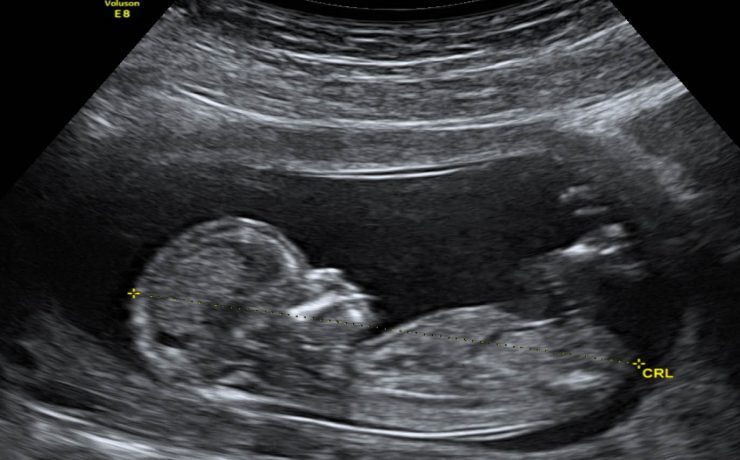

Recomendaciones Prácticas para un Examen de Ultrasonografía

En primer lugar se deberá preguntar si presenta alguna molestia y si su vejiga urinaria se encuentra muy distendida. También se deberá cuestionar sobre la razón por la cual el médico tratante ha solicitado el examen. Se preguntará sobre exámenes complementarios tanto de imagen